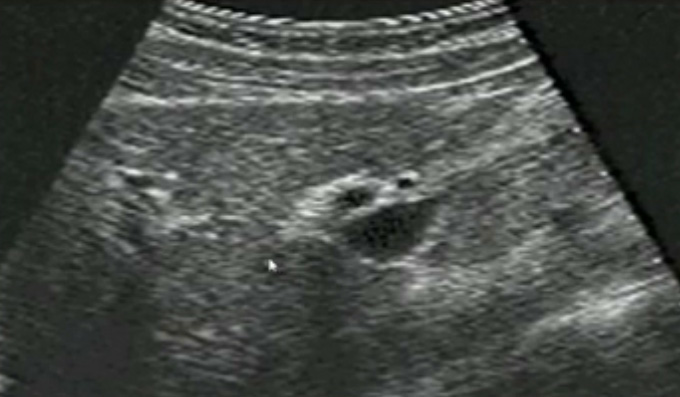

二、正常胆管超声图像

肝内胆管-无胆管扩张的情况下,超声一般只能显示胆管的一、二级支,不能显示二级以上的肝内胆管肝外胆管(声像图上大致分为两段)上段与门静脉伴行,位于门静脉主干的右前方;下段与下腔静脉伴行并延伸进入胰头背外侧。胆道、肝动脉与门静脉的关系。